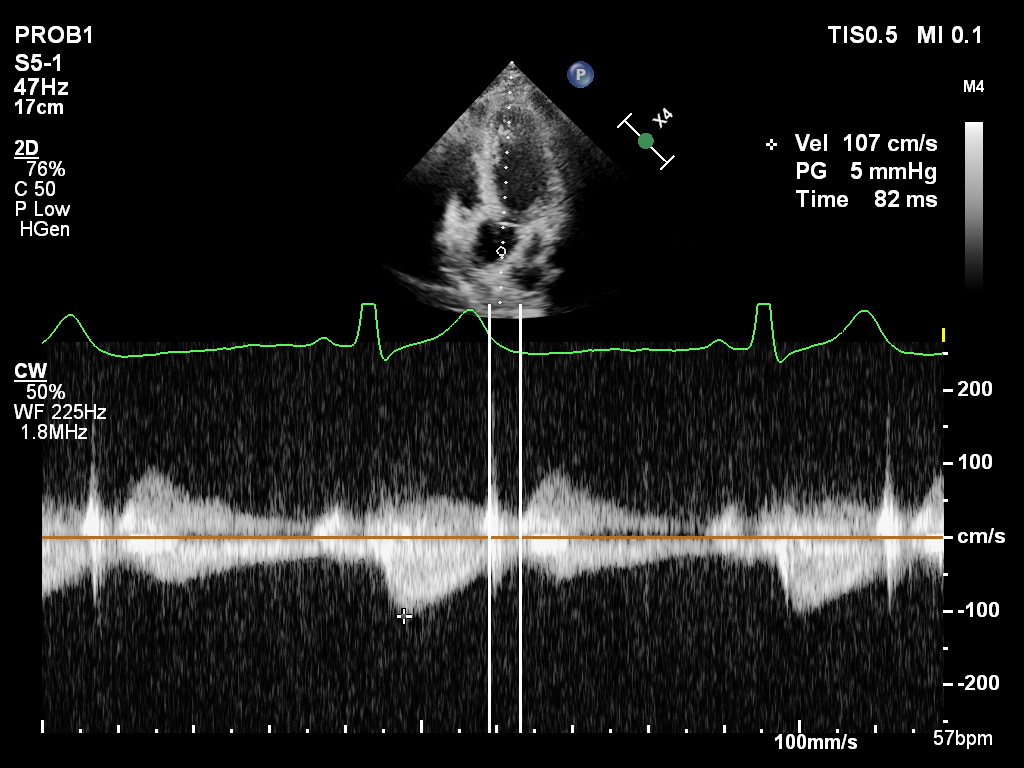

This is an important case for diastolic function assessment that was corrected in 2025 guideline. A main lesson is " Diastolic Function can be normal with reduced EF and/ or myocardial infarction." We should not adjudicate diastolic dysfunction based on clinical data. Always use…

24 y.o male, ejection fraction %40 after anterior infarction. E/A: 2,6 e': 11 IVRT: 82 msn diastolic dysfunction? @JaeKOh2 @AJamilTajik @EchoSoliman @DonalErwan @denisamuraru @PPibarot